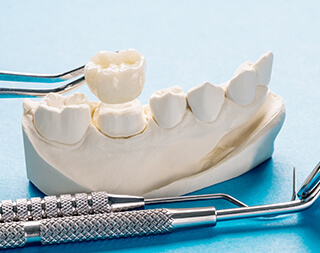

歯を補強するインレー(詰め物)・クラウン(かぶせ)などの歯科素材で、疾患部を除去した歯の状態に合わせて、補強します。審美的、機能的な材質を選びます。